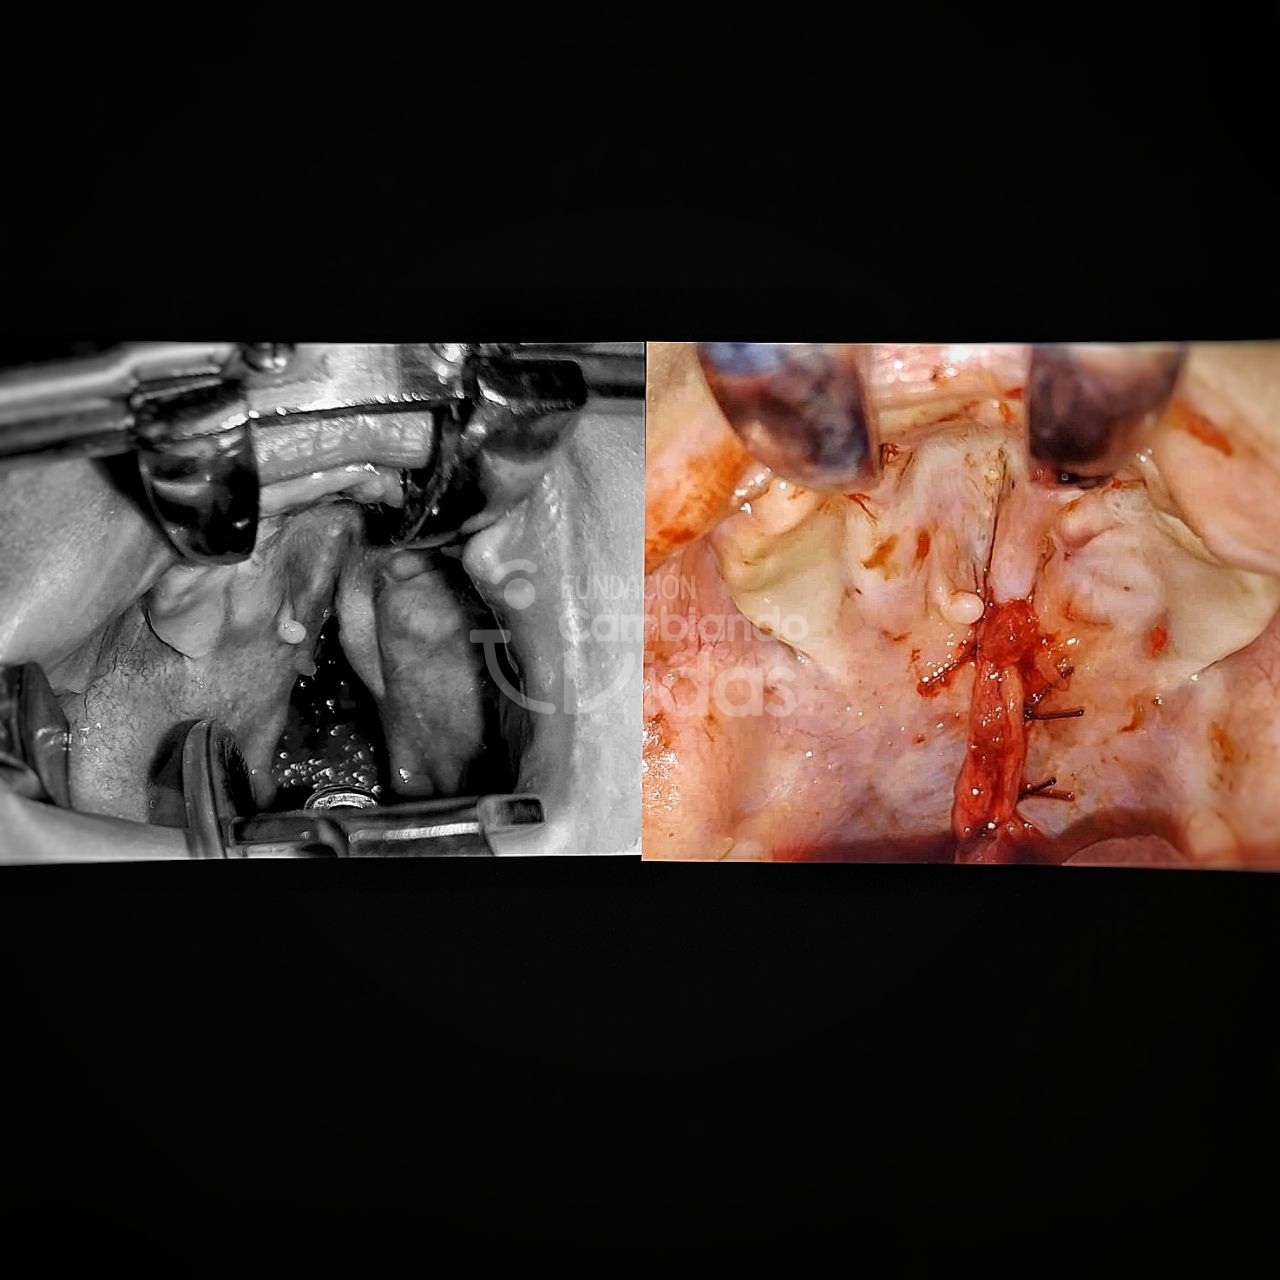

Esliange Pirela

Diagnóstico: Lactante Mayor de 1 año con Sindrome Genetico en Estudio y Hendidura Palatina

Intervención Quirurgica: Palatoplastia Primaria

Anyerson Garcia

Diagnóstico: Lactante Mayor de 1 año con Hendidura Labial Unilateral y Palatina Completa